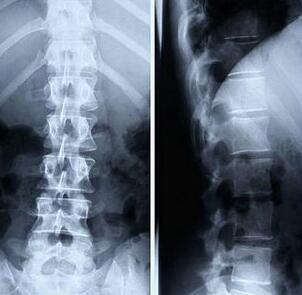

我院医生王怀庆主任接待了他,并安排其做了全身检查。检查结果:脊柱X线显示其骨质遭到破坏,胸腰椎和颈椎间小关节间隙模糊;红细胞沉降率增快为40mm/h,C反应蛋白(CRP)为30mg/l 。...[详细]